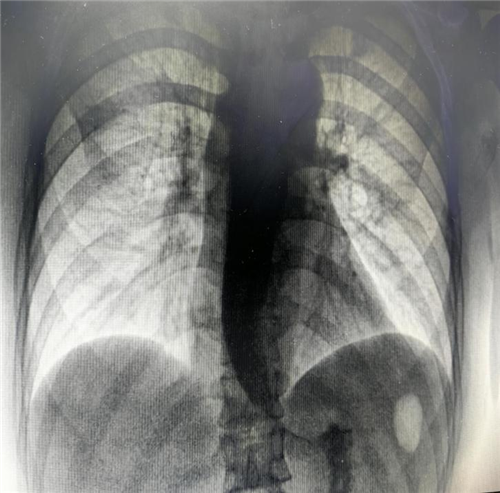

食管钡剂造影显示不同程度的食管扩张(钡剂潴留)以及食管下端变窄呈「鸟嘴样」改变,这是贲门失弛缓症的重要诊断依据。曾主任与患者及家属充分沟通后,决定为其施行 “内镜下贲门大球囊扩张” 治疗。该治疗的基本原理是将气囊置入食管内,再向气囊内注入气体,使其扩张到一定程度,使 LES 的肌纤维断裂,从而达到松弛 LES 的效果。术后,患者恢复良好。